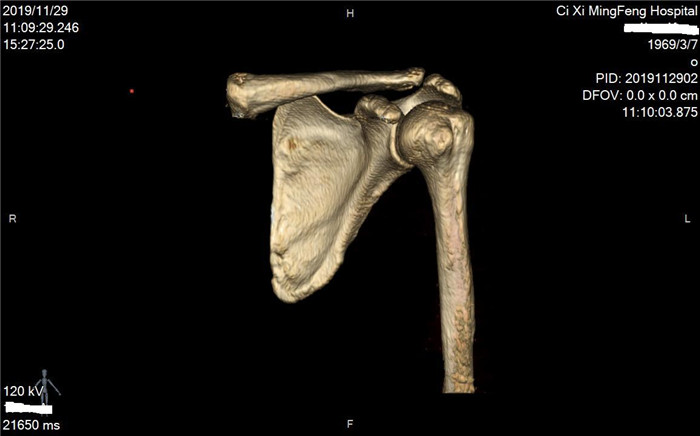

明峰CT搭載了領(lǐng)先的硬件技術(shù)平臺(tái)及系統(tǒng),強(qiáng)大的掃描能力可滿足臨床的各種要求,呈現(xiàn)更極致的細(xì)節(jié),為各臨床科室提供高品質(zhì)的圖像。薄層掃描,消除部分容積效應(yīng),提高各向同性。配合高分辨率算法,有助于細(xì)微結(jié)構(gòu)和形態(tài)學(xué)顯示。